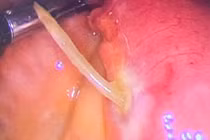

| Di vật được xác định là kẽm thường được làm hàng rào găm vào xuyên thủng phổi phải người bệnh. Ảnh: BVCC |